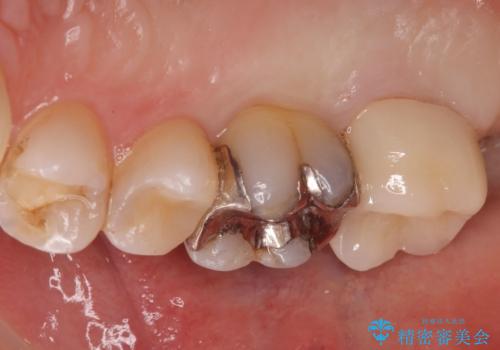

適合の良い被せ物が入りました。

冷たいものがしみなくなり大変満足してもらいました。

一つ前の歯も後に染みてくる可能性があるとの事で被せ物をするか検討中です。